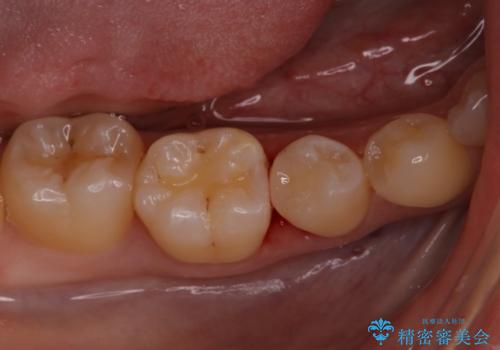

定期検診に来たら虫歯があった。

- 定期検診で歯のメンテナンスのため3ヶ月に1回来院されている患者様です。

最近フロスがよく引っかかるとのことでレントゲンを撮ったところ虫歯があり、セラミックインレーにて治療をすることになりました。